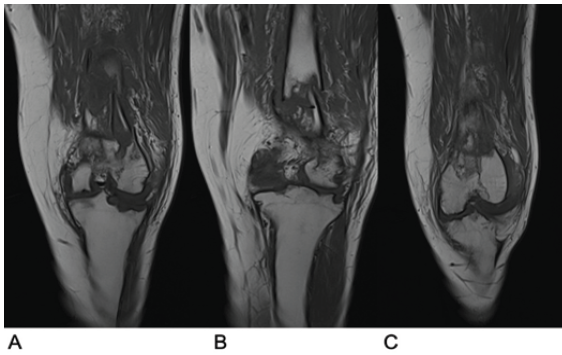

Three months after completing TB treatment, he sustained a comminuted fracture of the left distal femur following a fall resulting in excessive valgus force on the knee, as shown in the X-ray images in Fig. 3. A computed tomography scan (Fig. 4) raised concern over marrow sella tissue density and calcifications at the fracture site, suggesting an underlying lesion. Blood work during this period returned normal results (white cell count 8.7 × 109/L, CRP 3 mg/L).

Figure 3: X-ray images of the left knee following repeat injury demonstrating a comminuted left distal femur fracture. (a) Anterior-posterior view. (b) Lateral view.

Figure 4: Computed tomography scan of the left knee following repeat injury. (a) Axial view. (b) Coronal view. (c) Lateral view.

Figure 5: Magnetic resonance imaging scan of the left knee following repeat injury. (a) Coronal view of the anterior section of the joint. (b) Coronal view of the middle section of the joint. (c) Coronal view of the posterior section of the joint.

An MRI (Fig. 5) displayed normal marrow tissue and significant improvement in bony architecture compared to the initial MRI, with no suspicion of underlying lesions. A second open reduction and internal fixation was performed, with extensive samples taken for histological and microbiological analysis. Histological evaluations indicated acute inflammatory changes consistent with an acute fracture, and granulomas were absent. ZN staining and mycobacterial tissue culture were negative, confirming no recurrence of TB infection. The patient had a normal recovery following this surgical intervention, with tissue samples confirming successful treatment of TB. X-rays showed satisfactory alignment and implant placement (Fig. 6). The patient was pain-free while weight-bearing with one crutch at 12 weeks after the final surgery.